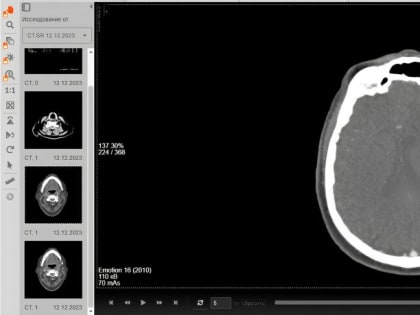

Уральские врачи удалили у пациентки большую опухоль в коре головного мозга и вернули женщине способность говорить

Нейрохирурги Городской больницы № 1 (ГБ № 1) Нижнего Тагила вернули 78-летней пациентке способность разговаривать.